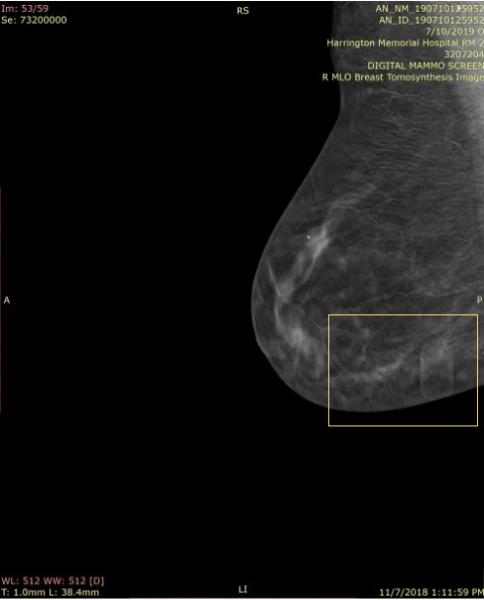

In particular, because they are larger than calcifications and clips, the skin markers3 that were used to indicate skin lesions, scars, sites of a palpable mass or pain caused significant artifacts called a ring down effect that caused distractions and limited visibility of underlying tissues.

“The biggest problem with the 2-D markers being used on the 3-D examinations is the ‘ring-down’ or ‘slinky effect’ that actually limits visualization of adjacent and underlying tissues, and is distracting, making one look at the artifact instead of the adjacent tissues,” she explained.

This ring-down effect is one of the reasons why Beekley Medical pioneered the first skin markers developed specifically for digital breast tomosynthesis. Some facilities stopped using skin markers due to this slinky-like artifact; but losing the visual communication skin markers provide did nothing to shorten radiologist read time.4

Responsive to customer needs, Beekley Medical partnered with early adopters of 3-D mammography to develop mammographic skin markers that would image well in order to convey critical information of surgical scar location, skin lesions, palpable areas, and other areas of concern under both the 2-D and 3-D portions of the DBT exam with minimal-to-no “slinky” artifact. Field-tested TomoSPOT skin markers for 3-D digital breast tomosynthesis were introduced in 2014 — the first markers specifically made for DBT technology.

According to Baum, “The 3-D markers as seen on the 2-D images are less bright, and also less distracting, when reviewing these images. They don’t have all the lines the old one had (referring to 2-D markers). The old ones had marks all the way through the breast. The lines with these (3-D markers) are less bright and you can still see the tissue through it. I don’t have to go through the images 2 or 3 times to get around the artifact — it takes longer to look harder in the areas where there is the slinky effect so as not to miss things — especially calcifications. The TomoSPOT skin markers result in a faster reviewing time of the 3-D image for me, as I don’t have to spend extra time looking in the area of the artifacts caused by the old markers.”